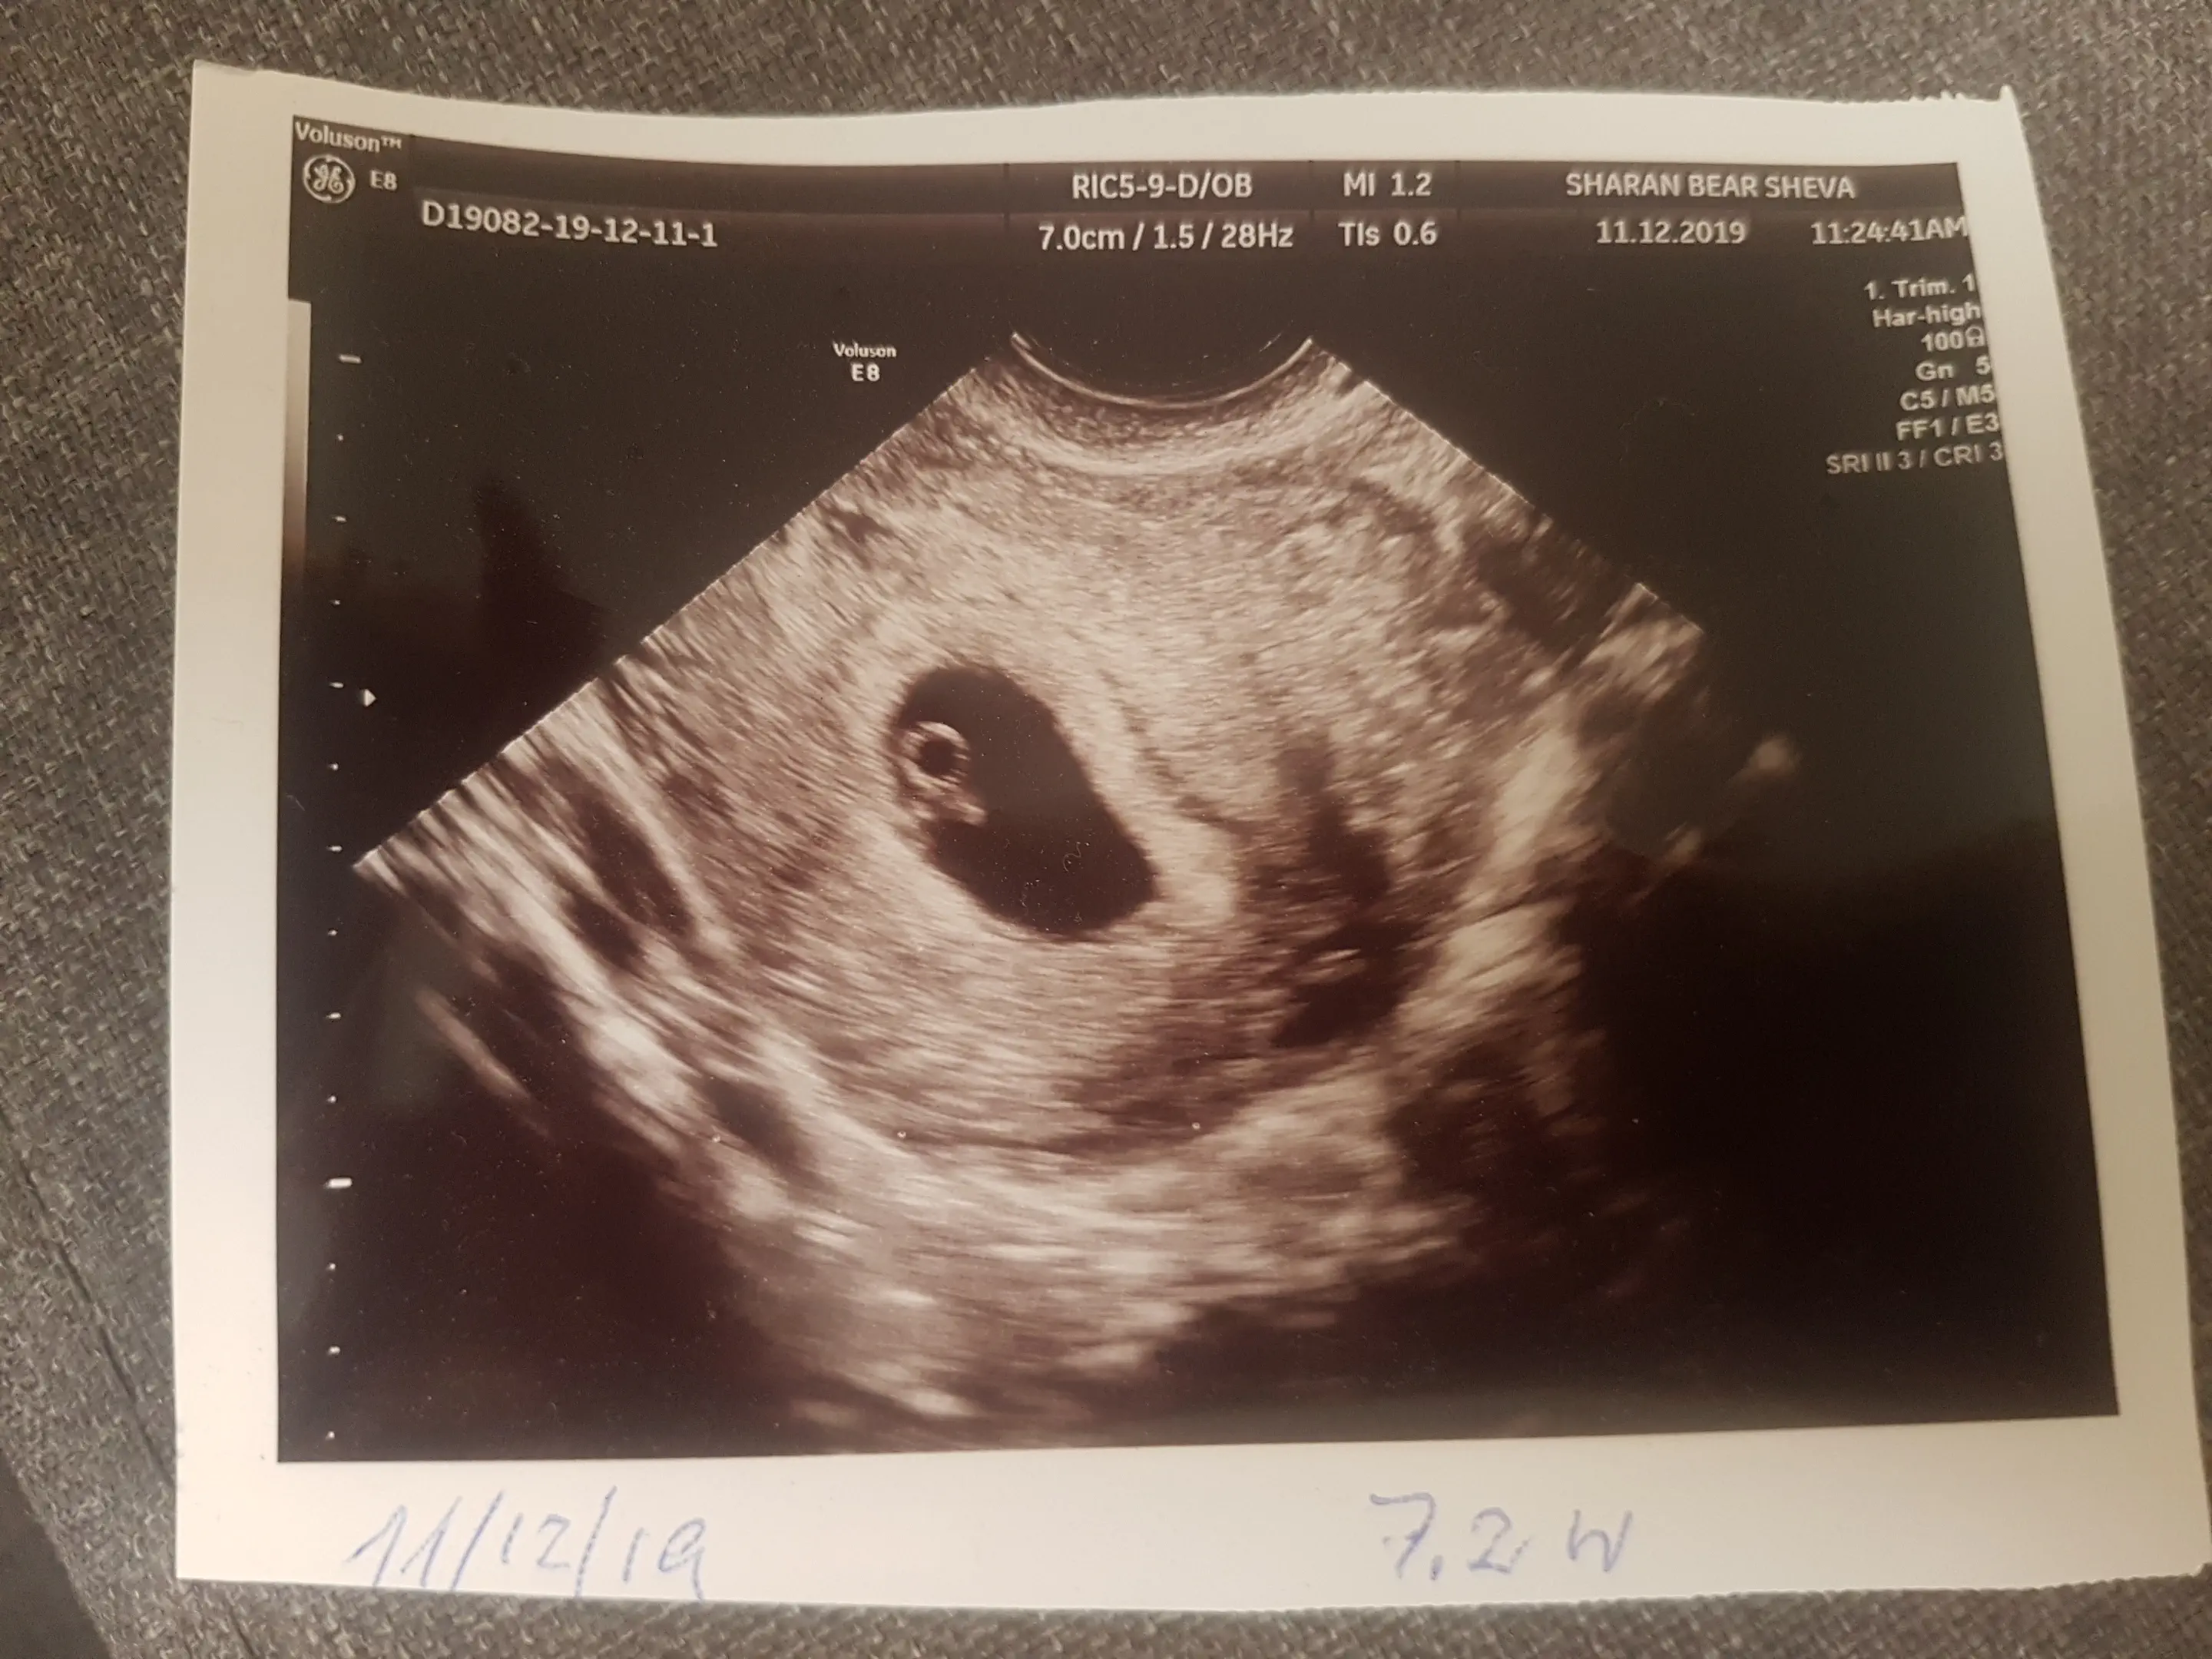

איך אני יודעת שהגודל שלו תקין?לאלי11

רשום לך למטה 7.2 שבועות הרופאה רשמה?בתי 123

כן... עשיתי יום רביעי וזה מה שהיא כתבהלאלי11

אז לפי האולטרסאונד מדדו את השבוע הזהבתי 123

לא מודדים גודל אלא שבוע

שיהיה המשך הריון קל ותקין

הבנתוש.. טוב אז מעולהלאלי11

אם זה אולטראסאונד ראשון אז הגודל תמיד תקין ולפיו קובעים את גיל ההריון (במקרה שאין התאמה לגיל לפי וסת אחרונה).